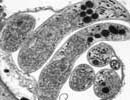

Cryptosporidium_hominis_30974 Courtesy of Saul Tzipori, Tufts

Comment:Cryptosporidium hominis is the dominant species which infects humans. Although generally self-limiting, this disease can cause fatalities in children and immunocompromised adults. The genome sequence of Cryptosporidium hominis shows features consistent with its life cycle as an obligate parasite. This organism lacks the genes necessary for the production of a number of biochemical building block such as nucleotides and amino acids. To compensate for this lack, the genome contains a large number of transporter or transporter-like genes.